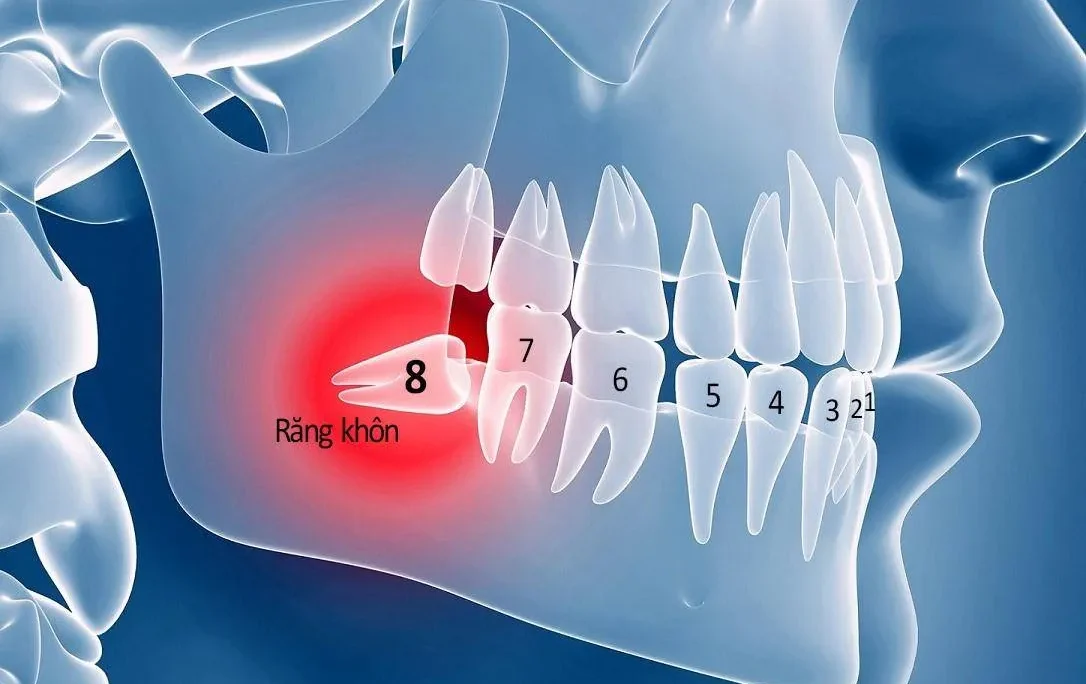

Phần tủy răng sẽ kéo dài từ chân răng cho tới phần thân răng. Nhìn chung, kết cấu của tủy răng khá phức tạp. Tủy răng được bao bọc và bảo vệ bên ngoài bởi ngà răng và men răng. Bên trong tủy có chứa nhiều mạch máu cũng như nhiều dây thần kinh. Cụ thể, tủy răng bao gồm 2 phần: ống tủy và buồng tủy. Trong đó, ống tủy nằm ở vị trí dưới cùng của răng và buồng tủy nằm ở thân răng.

- Răng bị sâu vỡ dẫn đến viêm tủy: Thường thì khi răng bị sâu vỡ, chúng ta dễ dàng quan sát và phát hiện vấn đề này. Tuy nhiên, cũng có những tình huống, răng bị vỡ ngầm dưới dạng các vết nứt. Những vết nứt này khó thấy bằng mắt thường và chỉ có thể nhận ra khi chụp X-quang. Khi sâu răng không được chữa trị kịp thời, vi khuẩn có thể xâm nhập vào tủy răng. Từ đó gây ra viêm nhiễm và đau đớn, đồng thời đối mặt với nguy cơ hoại tủy răng.

- Hệ thống tuần hoàn trong ống tuỷ bị gián đoạn: Nguyên nhân này giải thích tại sao một số người có thể trải qua chấn thương răng trong tuổi thơ nhưng khi họ trưởng thành, răng của họ bắt đầu thay đổi màu sắc sang nâu. Những chấn thương nhỏ trong quá trình phát triển có thể gây đứt các mạch máu tại vùng chóp. Từ đó làm cho tủy không còn được cung cấp dưỡng chất và dần dần hoại tử. Dấu hiệu thường thấy của tủy bị tổn thương là khi răng chuyển sang màu nâu.